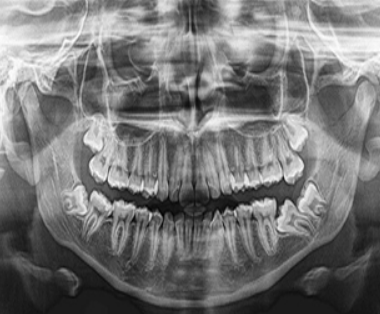

Os técnicos de radiologia são profissionais de saúde que efetuam exames na área da radiologia, ou seja, atuam na produção de imagens do interior do corpo que permitem diagnosticar situações patológicas como pneumonias, tumores ou fraturas ósseas, entre outras. As suas principais funções consistem na programação, execução e avaliação de todas as técnicas radiológicas utilizadas no diagnóstico, na prevenção e promoção da saúde, recorrendo, para esse efeito, a equipamentos tecnologicamente avançados.